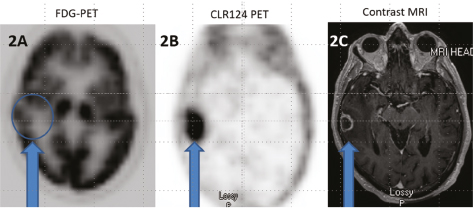

Fig 2

Figure 2. Axial 18F-FDG PET (2A), axial CLR124 PET (2B), and axial T1 contrast enhanced MRI (2C) in the same patient with a right temporal brain metastasis from non-small cell lung carcinoma. Note the high background cerebral uptake of FDG limits identification of the metastasis on 18F-FDG PET whereas the high tumor uptake compared to low background cerebral uptake of CLR124 facilitates easy identification of the metastatic lesion. The lesion is demarcated by arrows on all images and demonstrates enhancement on MRI.